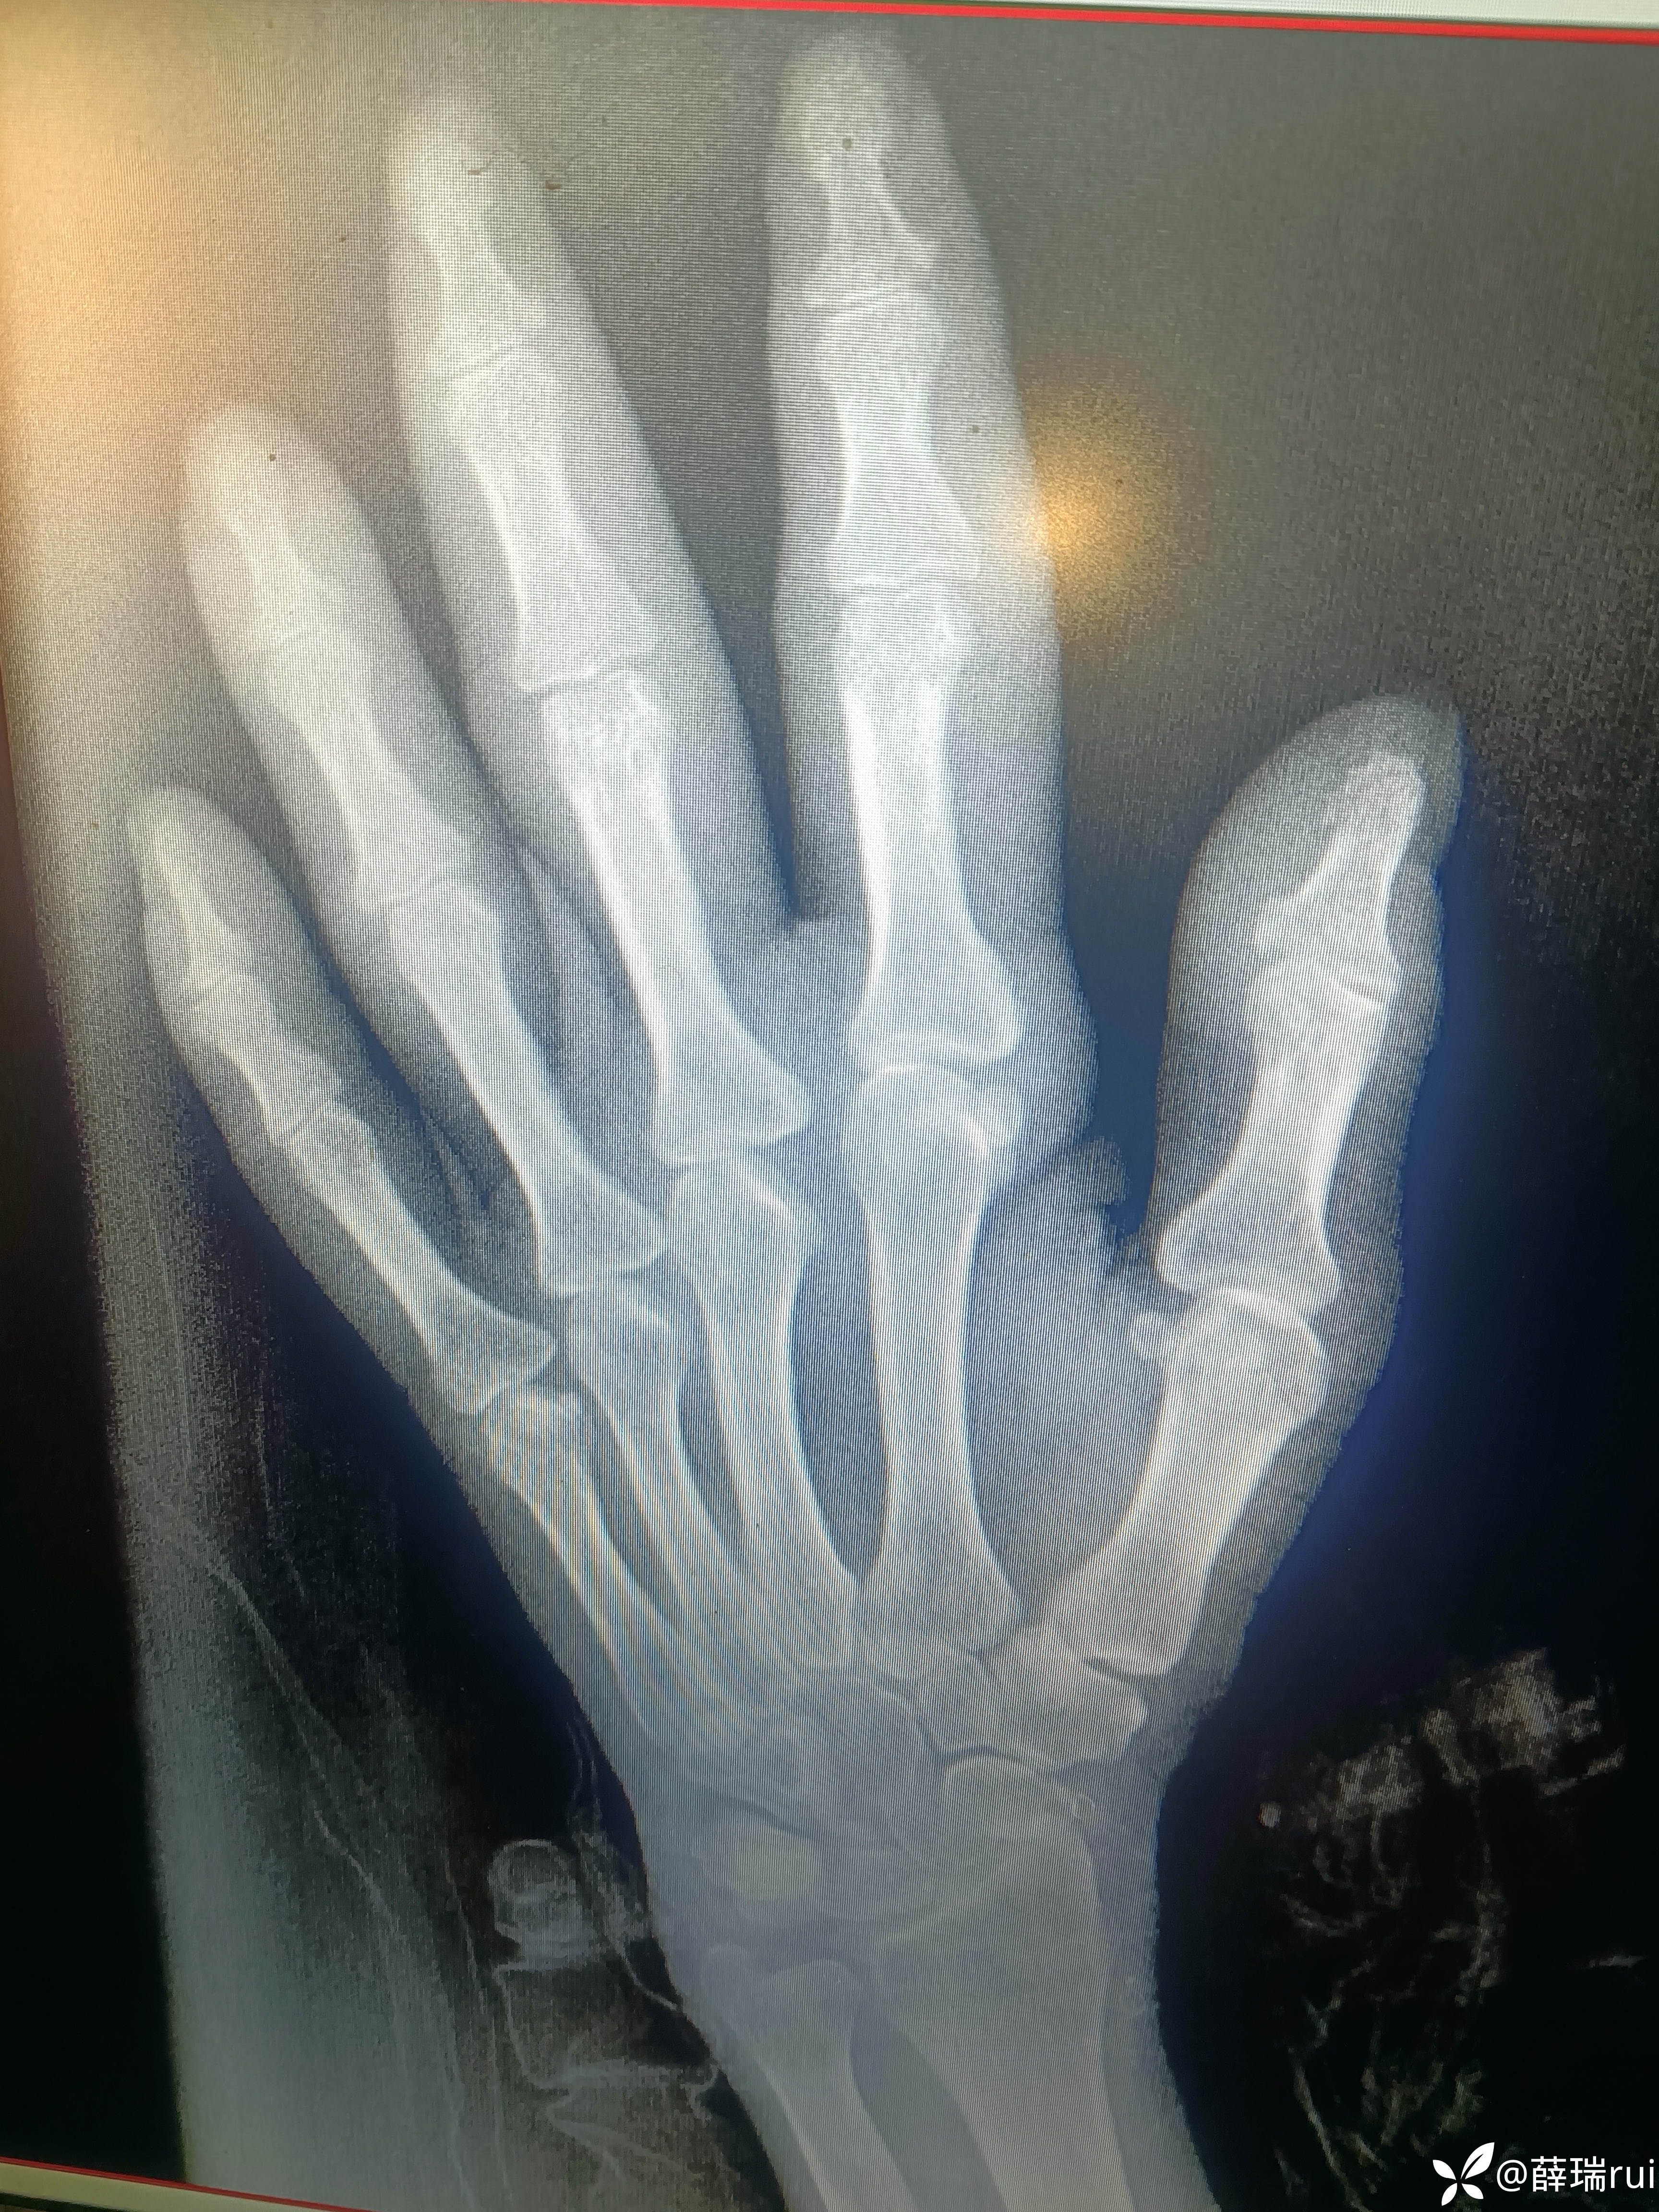

【患者信息】:女 55岁

【主诉】:咳嗽,纳差四肢手足指(趾)紫绀坏死3天。

【检查】